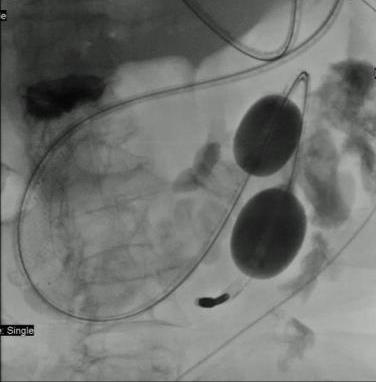

• 超声内镜引导下胃旁曲张静脉精准断流术治疗食管胃静脉曲张出血的疗效分析(附20例报告)

2025, 31(8):85-90. DOI: 10.12235/E20250036

摘要 (153) HTML (42) PDF 5.38 M (98) 评论 (0) 收藏

摘要:目的 探讨超声内镜引导下胃旁曲张静脉精准断流术治疗食管胃静脉曲张出血的疗效。方法 回顾性分析2024年1月1日-2024年12月31日于该院接受超声内镜引导下胃旁曲张静脉精准断流术治疗的20例肝硬化食管胃静脉曲张出血患者的临床资料,并评估治疗效果。结果 20例患者均顺利完成超声内镜引导下胃旁曲张静脉精准断流术;注射组织胶联合置入弹簧圈(16例)和单独注射组织胶(4例)均成功阻断胃旁来源的曲张静脉;所有患者均未发生穿孔、食管贲门狭窄、大出血、败血症和异位栓塞。1例单独注射组织胶的患者,术后胃旁曲张静脉少许渗血,经降低门静脉压力治疗3 d后好转,另1例单独注射组织胶患者,术后出现低热,抗感染3 d后体温恢复正常。结论 超声内镜引导下胃旁曲张静脉精准断流术治疗食管胃静脉曲张出血的临床疗效好,异位栓塞、大出血、感染和穿孔等并发症少,但仍需要密切随访,观察胃旁曲张静脉的排胶问题。